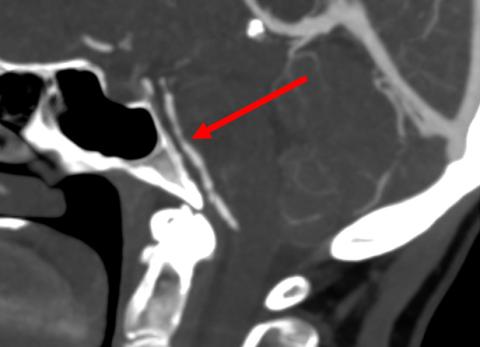

Sagittalt snit af arteria basilaris med karspasmer (pil). Tegnet kaldes »perler på en snor« og er klassisk for reversibelt cerebralt vasokonstriktionssyndrom.